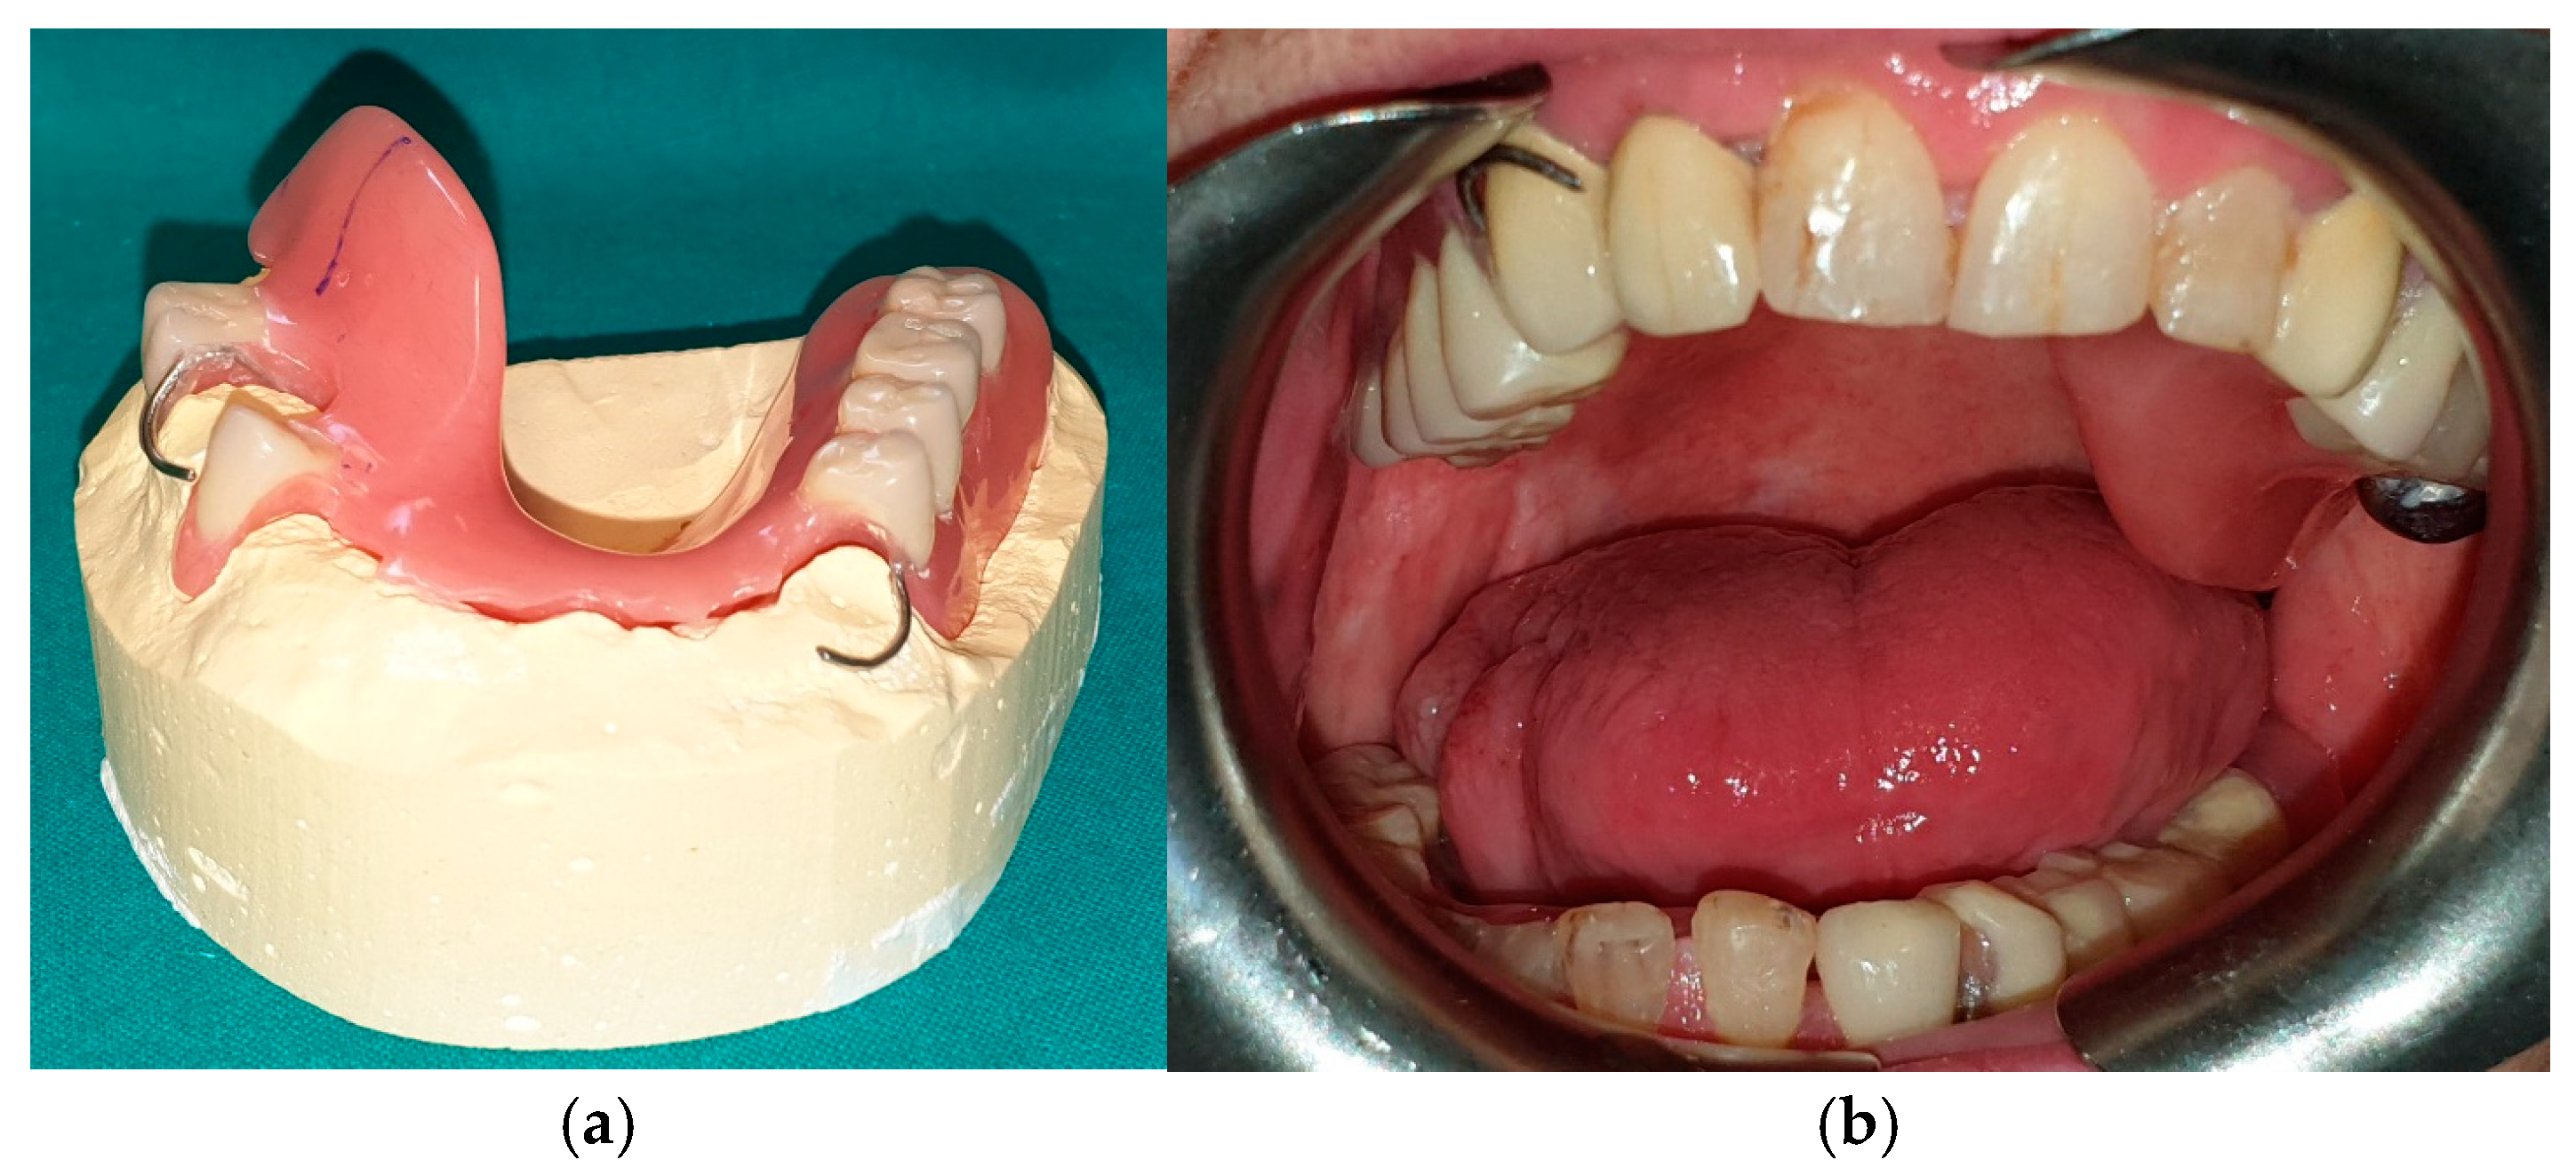

The patient of case 2 presented an L2-3 resection, with preservation of both the condyle and the coronoid process (Figure 5 and Figure 6). Although posteriorly edentulous, the patient had maintained six lower elements (31, 32, 33, 34 (which hosts a prosthetic crown), 41, and 42). The trajectory between open and closed positions is roughly maintained, and the surviving mandible does not tend to swing laterally toward the surgical side during opening (Figure 7).

Figure 5. Patient with hemimandibulectomy L2, L3 in extra- (a) and intraoral (b) view.